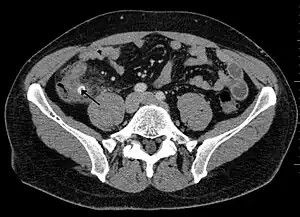

![]() Fecaloma rectal en un paciente hospitalizado. Presenta, además, una neovejiga y aterosclerosis. TC abdominal. | ||